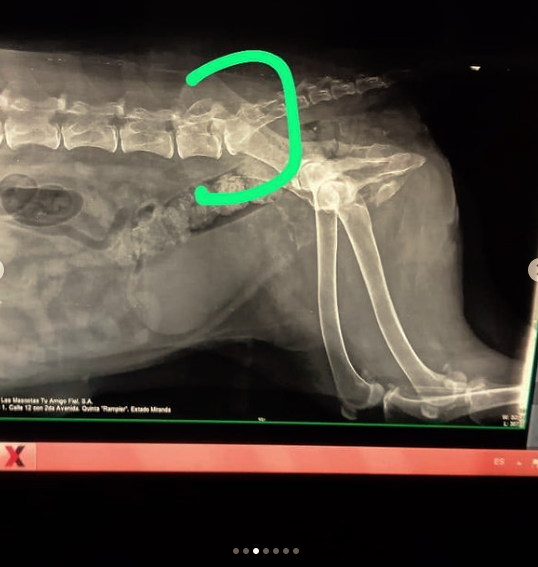

Bianca es una perra samoyedo que parece un copo de algodón flotando cuando la ven pasar junto a su manada. Ella es buena, noble, inteligente y por esa actitud de perra sabia y dulce que le han dado los años se ha ganado el amor y respeto de los vecinos de Montalbán, donde suele pasear todas las tardes o noches junto a sus hermanos perros donde ejerce una especie de matriarcado de perra Alfa. Anoche Bianca fue atropellada por una persona que en su afán para entrar al estacionamiento de uno de los edificios de Juan Pablo II, la arolló, ante los ojos de amigos que vieron impotentes como la camioneta le pasaba por encima, Bianca que ya venía sufriendo de displasia de caderas, se encuentra ahora en su casa sufriendo y sin poder caminar, ya se le puso una inyección para calmar sus dolores, pero para saber que problemas atraviesa debido al accidente y si tiene alguna fractura, o hemorragia interna se le debe hacer una radiografía de tres vistas, así como pagar la consulta y su posible operación.

Bianca se encuentra postrada, no puede caminar y tiene retención de orina, así como inflamación de hígado.